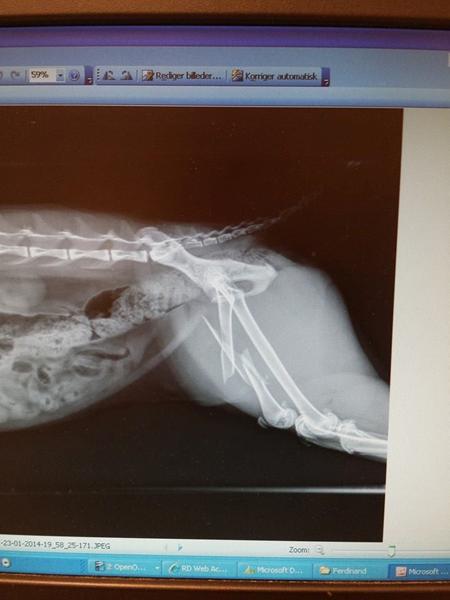

vi troede faktisk "bare" at det var hoften som var gået af led. men det viste sig på røntgen at det var værer end det

han havde simpelthen brækket lårbensknoglen

sådan ser det ud